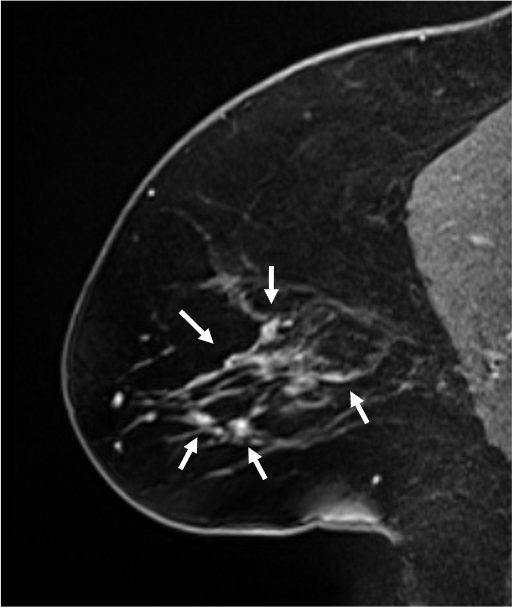

5. Ultrafast DCE

超早期相では、DCISの病変(矢印)は、超早期(8相目: 造影剤注入25.7秒後)から急速に造影され、BPEの影響を受けることなく病変を認識することができる。DCISの病変は、区域性の分布を示しているが、乳頭下には腫瘍の進展を疑うような造影域は認めない。